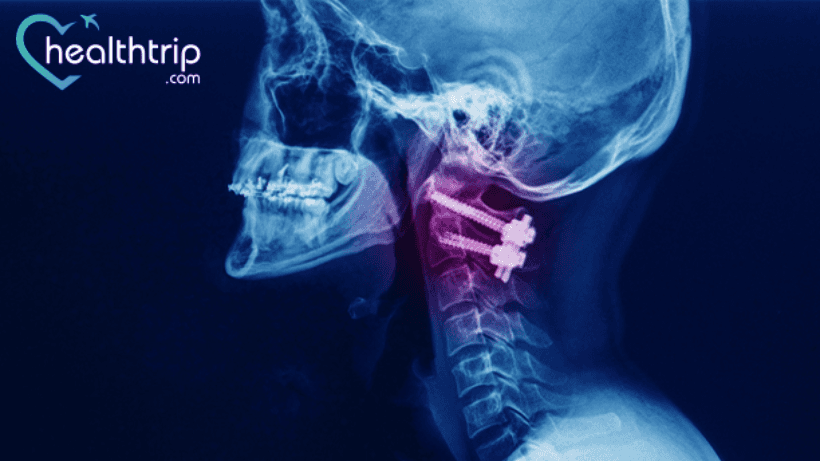

When considering spine surgery, it is important to do everything possible to correct the problem for the very first time. During the first surgical procedure, the chances of success are always higher. However, after any kind of spine surgery, a percentage of patients may still experience intractable pain or other complications. This is called a "failed back" or "failed fusion surgery." Here we’ve discussed the causes and the signs of failed fusion surgery with our expert spine surgeons.

One such commonly performed spinal fusion surgery is Anterior Cervical Discectomy and Fusion Surgery(ACDF).

Cervical fusion surgery has been very successful for many people. People who did not have a good outcome from their surgery experienced increased neck pain, neck instability, and bone spurs. In some cases, they have also been advised that more fusion is required for fixing the failed one.

As per our expert spine surgeon, the following are the symptoms of failed cervical fusion surgery:

In these cases, more surgery was required to fix such issues. The patients underwent a successful atlantoaxial and C2-C3 fixation, and they were able to walk independently again 21 months after the new surgery.